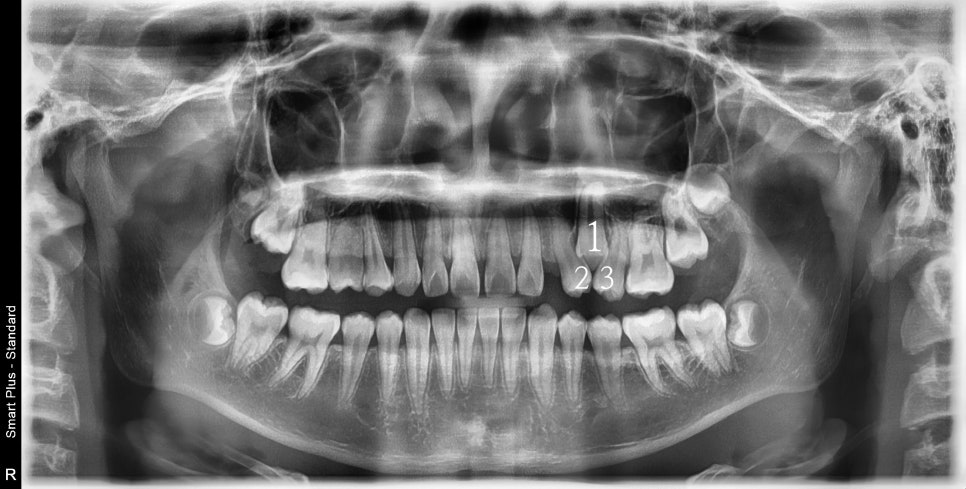

사진상 2 1 3 이라고 표시된 치아의 원래 순서는 1 2 3 입니다.

가끔 이렇게 치아가 만들어지면서 치아의 씨앗 위치가 바뀌면서 뒤죽박죽이 되는 경우가 있습니다.

어느정도라면 원래의 순서로 배열하기도 하지만, 이 친구는 2 1 3 순서로 배열하기로 했어요.

23/10/18사진이지만 실제치료는 한달뒤인 11월말에 시작했습니다. 제작에 한달씩 걸리거든요.